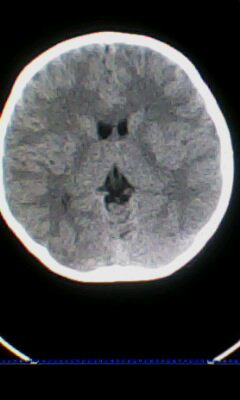

标题: PED3324:男 10岁 右侧 眼不自主抽动 自感颈部不适 [打印本页]

标题: PED3324:男 10岁 右侧 眼不自主抽动 自感颈部不适

蛛网膜下腔出血。

蛛网膜下腔出血可能。

颅脑ct轴位平扫颅内未见明确异常;建议必要时行mri检查。

窗调的不好,图像感觉怪怪的,不好说有什么明显异常,可建议mri检查。

颅脑ct轴位平扫颅内未见明确异常。